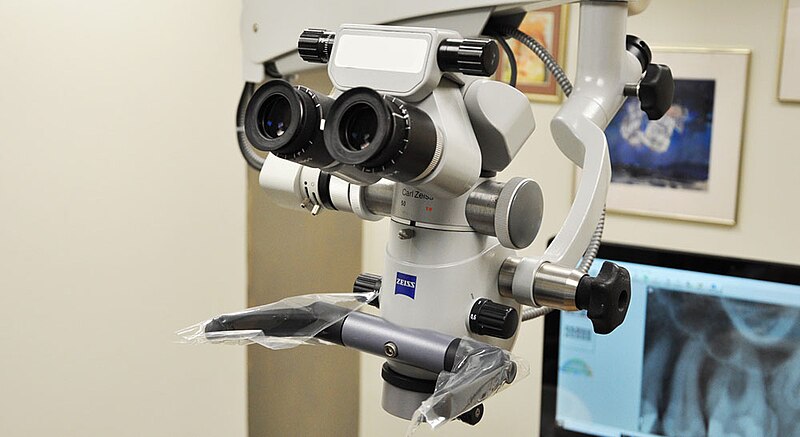

DU d'endodontie clinique et microscopie opératoire